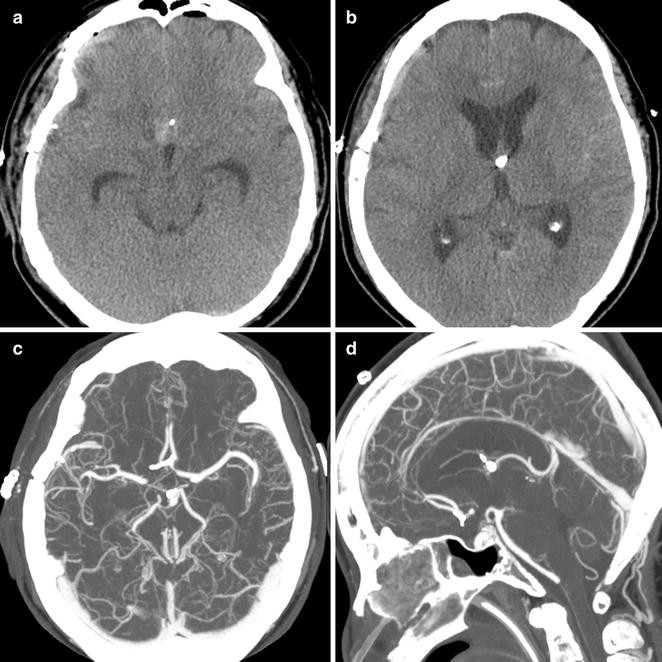

Medical & health in hanover, massachusetts. Brain aneurysm repair is a surgical procedure used to treat a bulging blood vessel in the brain that's at risk of rupturing or tearing open. There are two populations of aneurysm patients:

A brain aneurysm can be very painful and traumatic. Because each surgery varies, your brain aneurysm surgery recovery will vary depending on the an aneurysm is a damaged or weakened area in the wall of an artery that supplies blood to the brain. Brain aneurysm repair is a surgical procedure used to treat a bulging blood vessel in the brain that's at risk of rupturing or tearing open. The brain aneurysm foundation presents recovery from an unruptured brain aneurysm. learn about what to expect in recovery after brain aneurysm clipping.